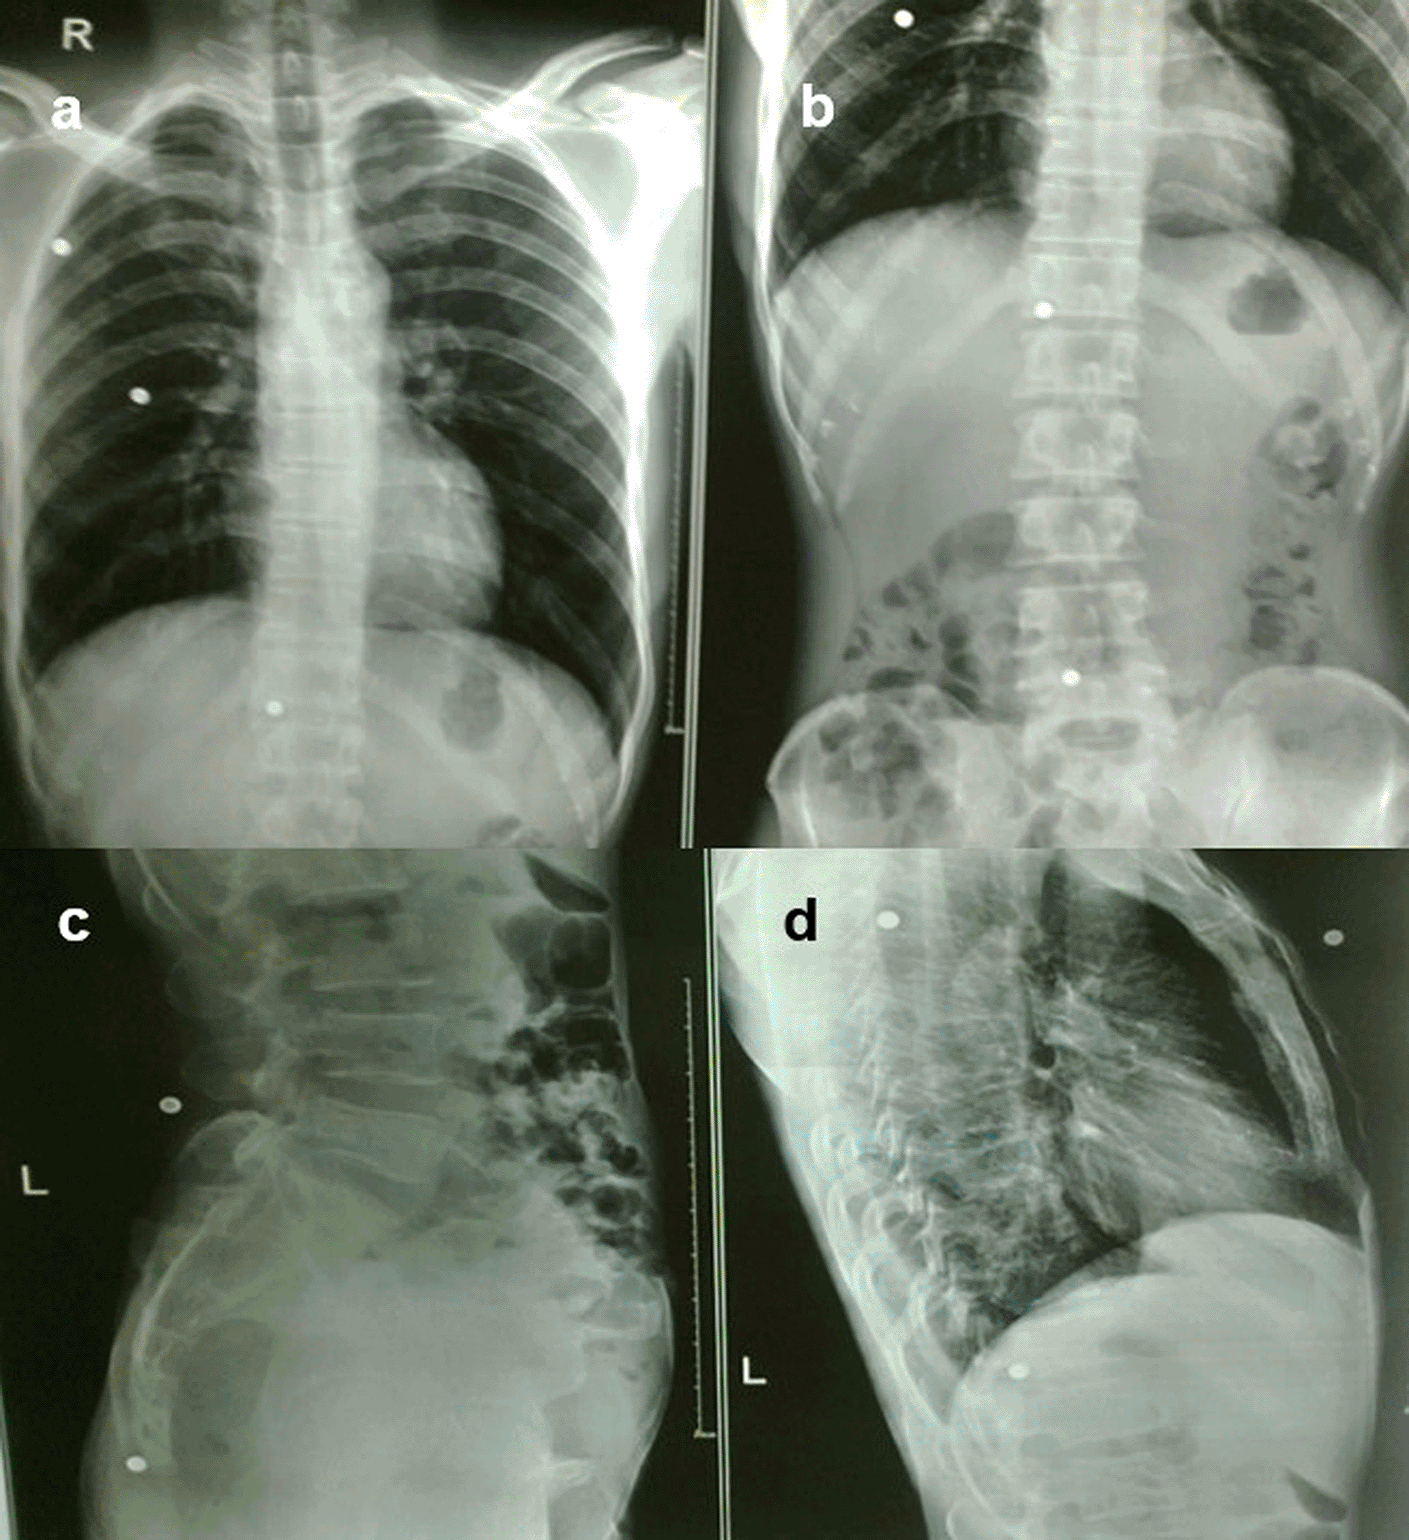

The gauge of a shotgun pellet determines its size, the higher the number, the smaller the pellet. Serious soft tissue and bone damage can result from the combined mass striking a target close to the gun barrel (Figure 9a-d). Because steel pellets are ferromagnetic, they could move dangerously if such a patient with embedded steel pellets was exposed to a magnetic field, making magnetic resonance imaging potentially dangerous.2